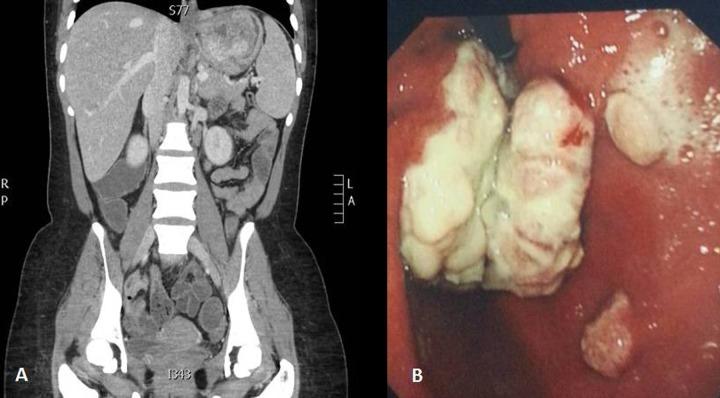

We report on a case of gastric GANT in a young female who was treated surgically by total gastrectomy. The disease, however ran an aggressive course with the development of distant (nodal, liver, lung, adrenal and musculo-skeletal) metastases two months after the radical resection.

我们报告一例年轻女性胃GANT病例,该患者接受了全胃切除术。然而,疾病进展迅速,根治性切除术后两个月出现远处(淋巴结、肝脏、肺、肾上腺和肌肉骨骼)转移。